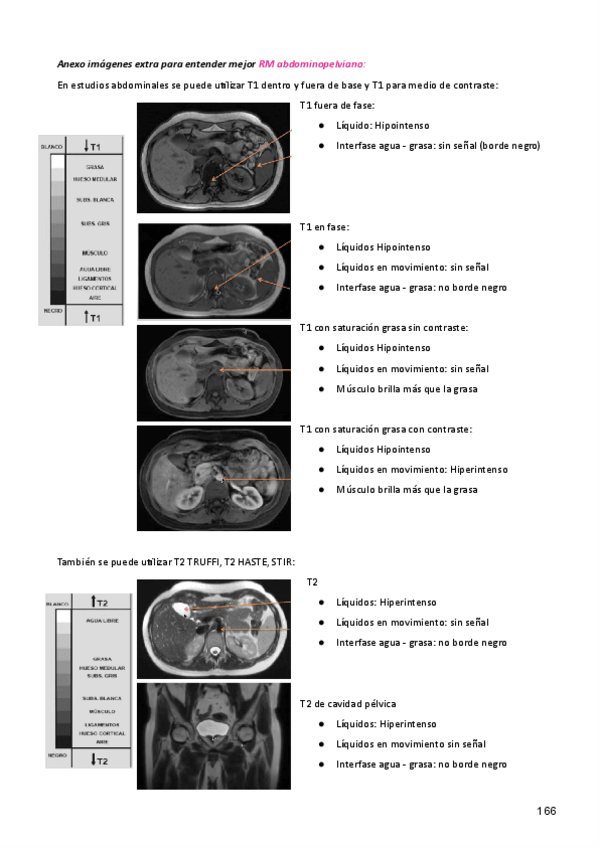

Incluye fotos del Netter, junto con imágenes tanto de TC como de RM

Anexo-TC-y-RM.pdf